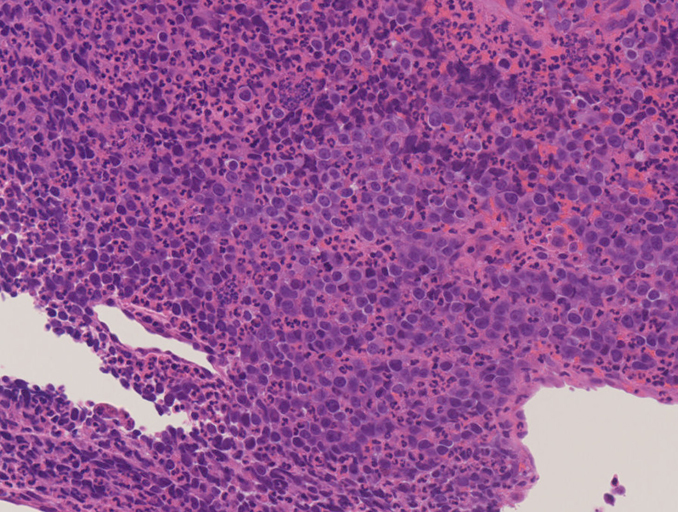

IWT case: 18 year old female.

副鼻腔腫瘤生検組織

日本病理学会中部支部交見会のスライドより。(S.Suzuki Dr.)

NUT03.jpg NUT04.jpg